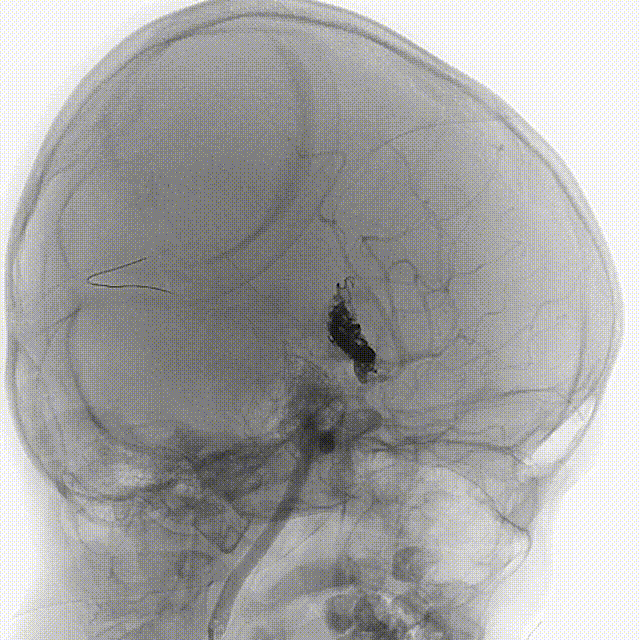

造影显示右侧豆纹动脉外侧组和内侧都有供血,经增粗引流静脉向直窦引流。